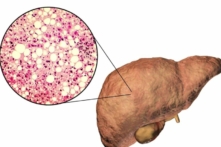

Viêm gan mỡ không do rượu (NASH) xảy ra trên người uống ít rượu hoặc không uống rượu, khi chất béo tích tụ trong gan.

Viêm gan gây ra NASH, dẫn đến tích tụ chất béo trong mô gan và hình thành mô sẹo, mô sẹo lâu ngày có nguy cơ tiến triển thành xơ gan – căn bệnh nặng có thể đe dọa tính mạng.